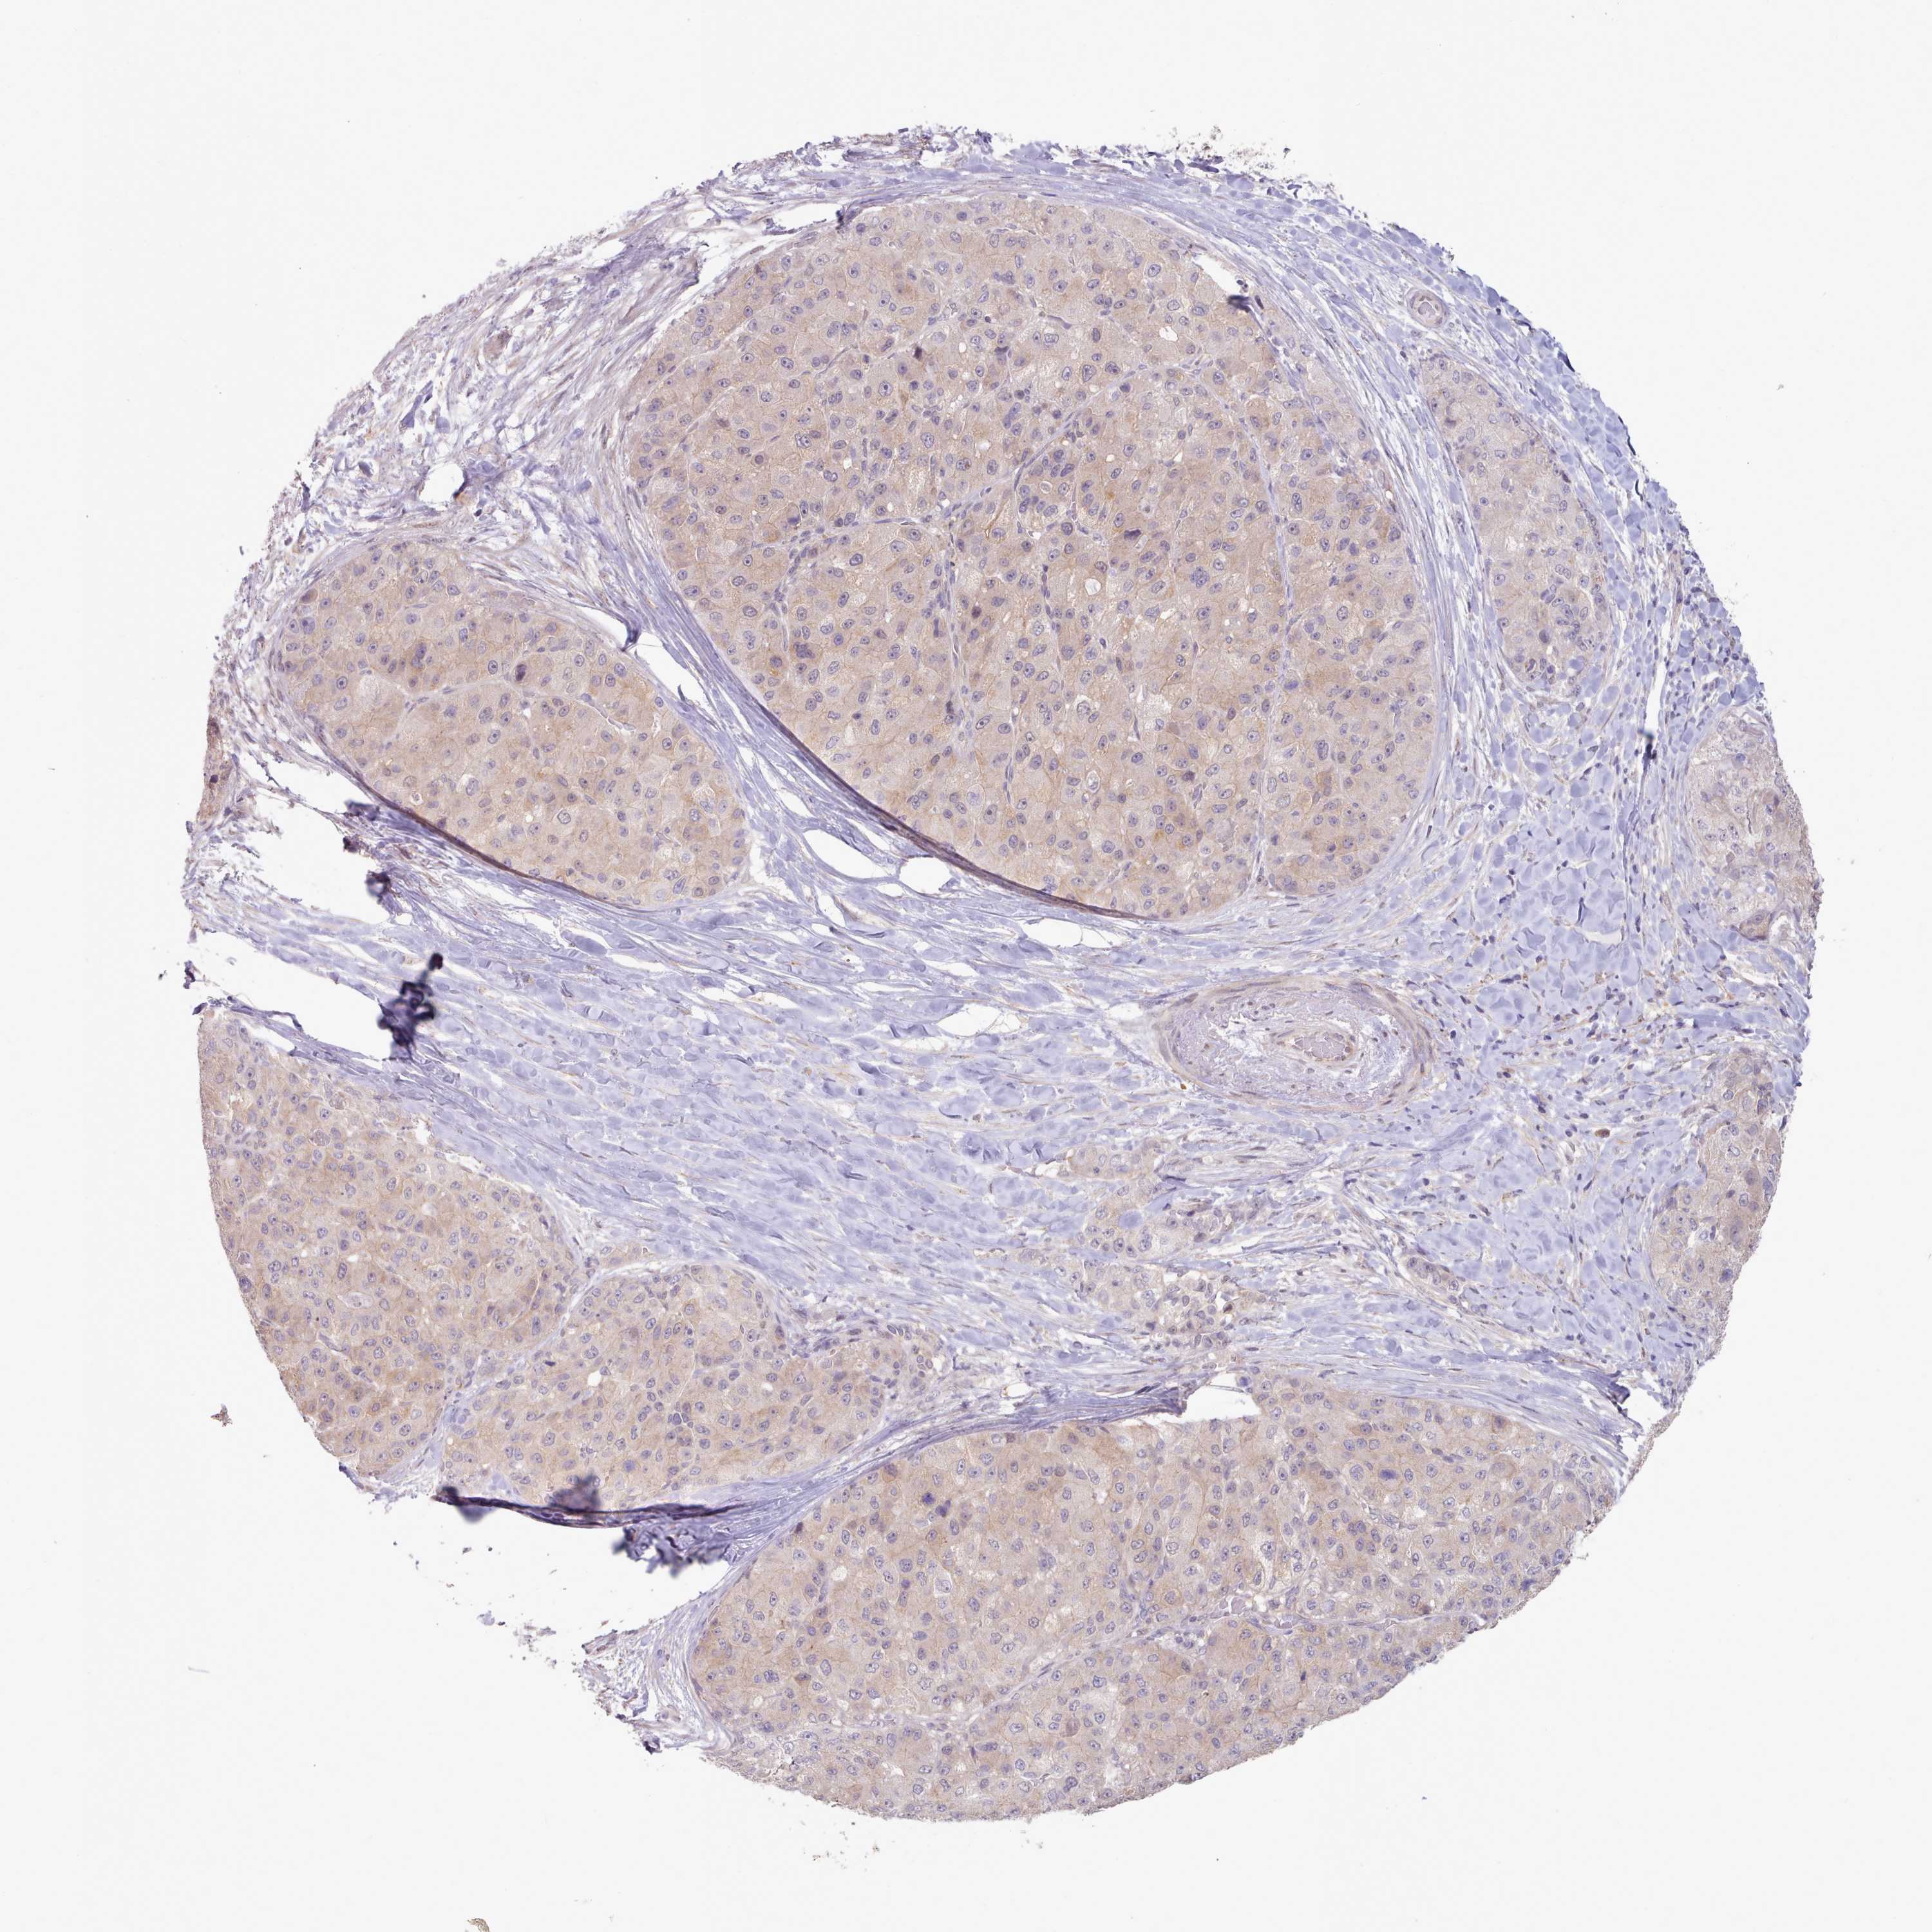

LIVER CANCER - Protein expressioni

A mouse-over function shows sample information and annotation data. Click on an image to view it in a full screen mode. Samples can be filtered based on level of antibody staining by selecting one or several of the following categories: high, medium, low and not detected. The assay and annotation is described here.

Note that samples used for immunohistochemistry by the Human Protein Atlas do not correspond to samples in the TCGA dataset.

Antibody stainingi

Antibody staining in the annotated cell types in the current human tissue is reported as not detected, low, medium, or high, based on conventional immunohistochemistry profiling in selected tissues. This score is based on the combination of the staining intensity and fraction of stained cells.

Each image is clickable and will lead to virtual microscopy that enables deeper exploration of all samples and also displays staining intensity scores, fraction scores and subcellular localization as well as patient and tissue information for each sample.

Antibody HPA041008

Antibody HPA041307

Staining

High

Medium

Low

Not detected

Intensity

Strong

Moderate

Weak

Negative

Quantity

>75%

75%-25%

<25%

None

Location

Nuclear

Cytoplasmic/membranous

Cytoplasmic/membranous,nuclear

Cholangiocarcinoma

Carcinoma, Hepatocellular, NOS